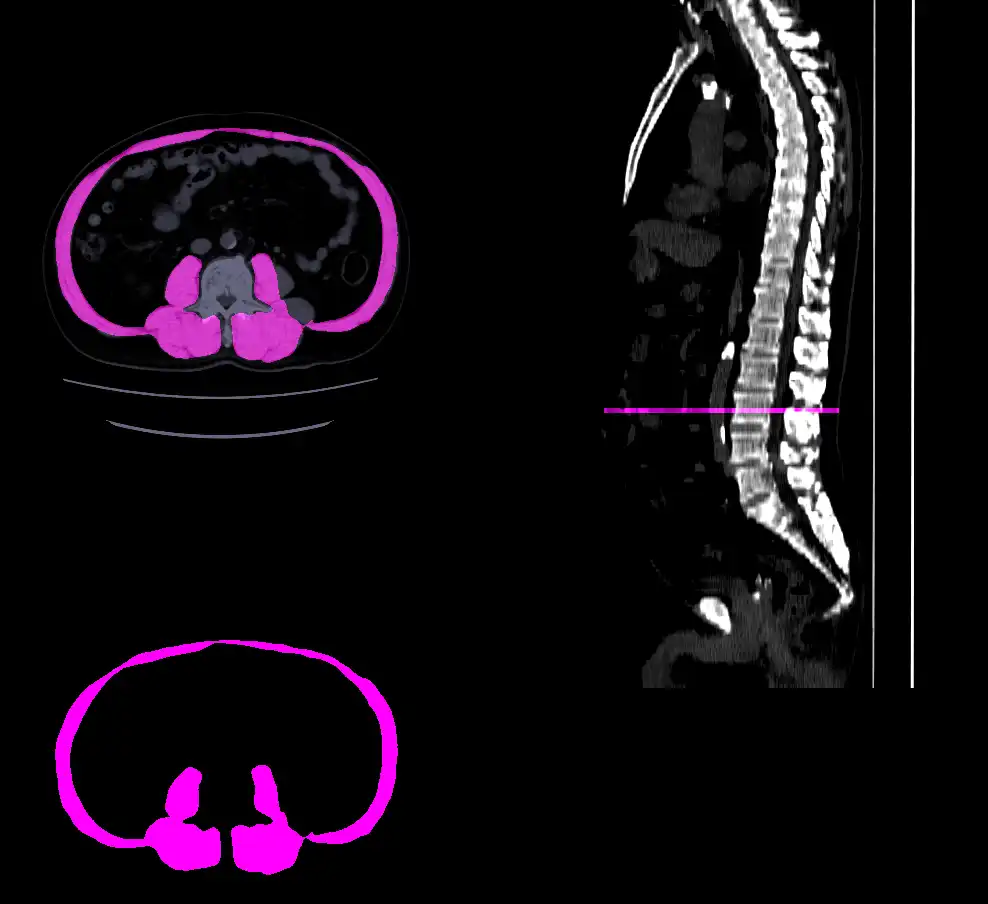

本研究室では、任意のCT画像から全自動でL3椎体中央レベルの骨格筋をセグメンテーションするツールを軸に、同レベルの内臓脂肪・皮下脂肪領域の抽出、各種統計値の抽出を行うシステムを確立しています。

この成果は、さまざまな加齢・疾患・術後予後予測タスクに応用される予定です。